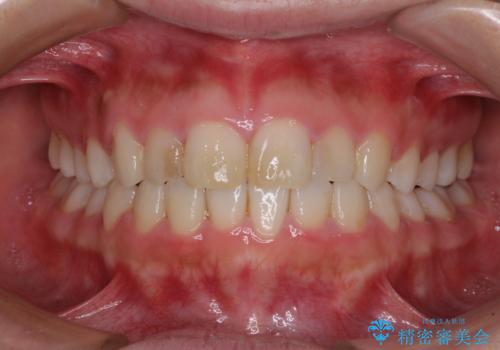

気になる前歯を治したい インビザラインで気づかれずに矯正治療

- ワイヤーではない矯正治療があると聞いたとのことで来院された患者様です。

長年前歯のデコボコを気にしていたもののワイヤー矯正に抵抗があり躊躇していたそうですが、インビザラインなら治療してみたいとのことで相談にいらっしゃいました。

インビザライン適用の歯列であったため、歯と歯の間を削るIPRを用いて改善することとしました。

お仕事柄、長時間のマウスピース装着が苦ではなかったので、歯列はすぐに整いましたが、ゆっくりとした交換頻度であったので、2年ほどの治療期間を要しました。